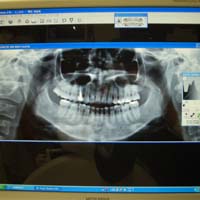

<デジタルレントゲン>

従来型と比べ、大幅に被曝量を抑えております。

デジタルなので、現像までの時間も短く、鮮明な画像により、さらに正確な診断が可能です。

患者様は、チェアーにお座り頂いたままで、ご自身の鮮明なレントゲン画像をご覧になる事が出来ます。

(上記画像の掲載につきましては、患者様よりご了承を頂いております)